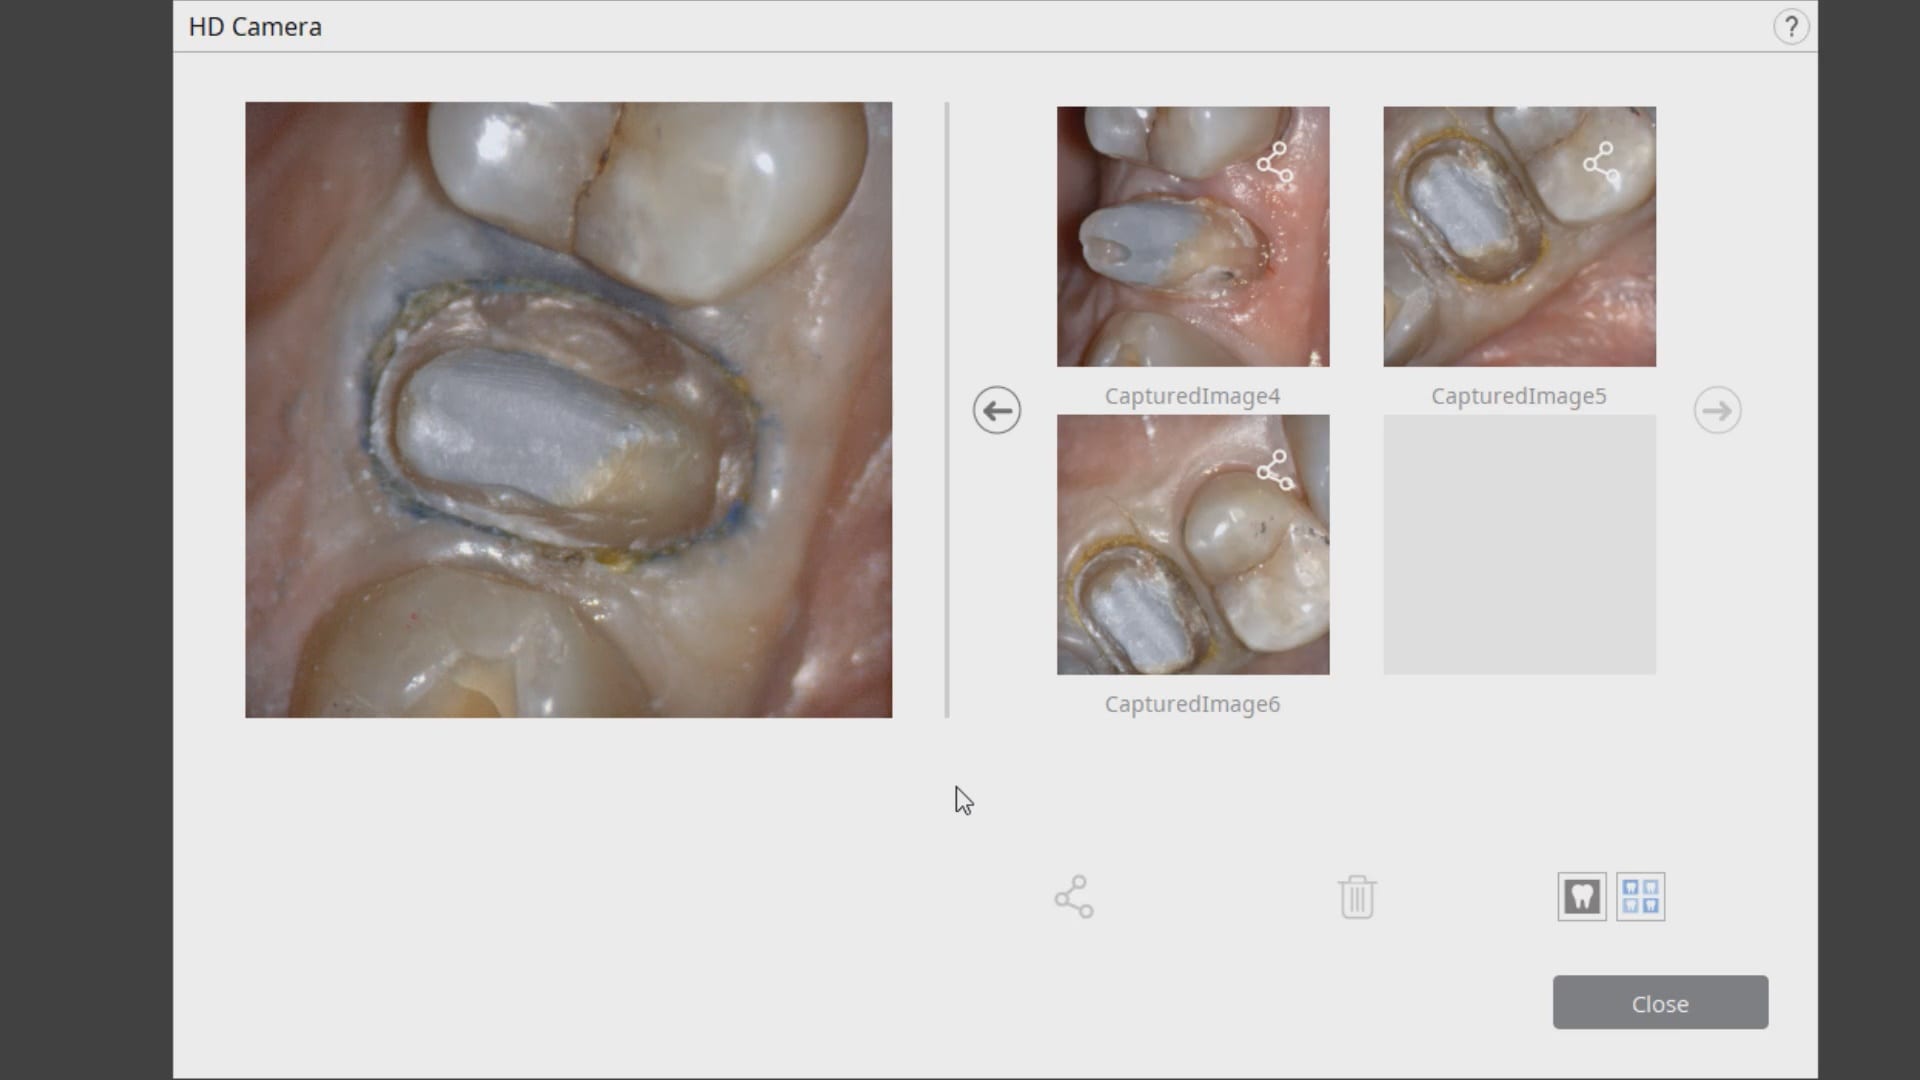

Case set up involved imaging the pre-existing condition in the pre-op catalog box. Excess information was cropped to reduce file size. The data was then copied to the maxillary arch catalog box and the area to prepared was edited out in preparation for final optical impressions.